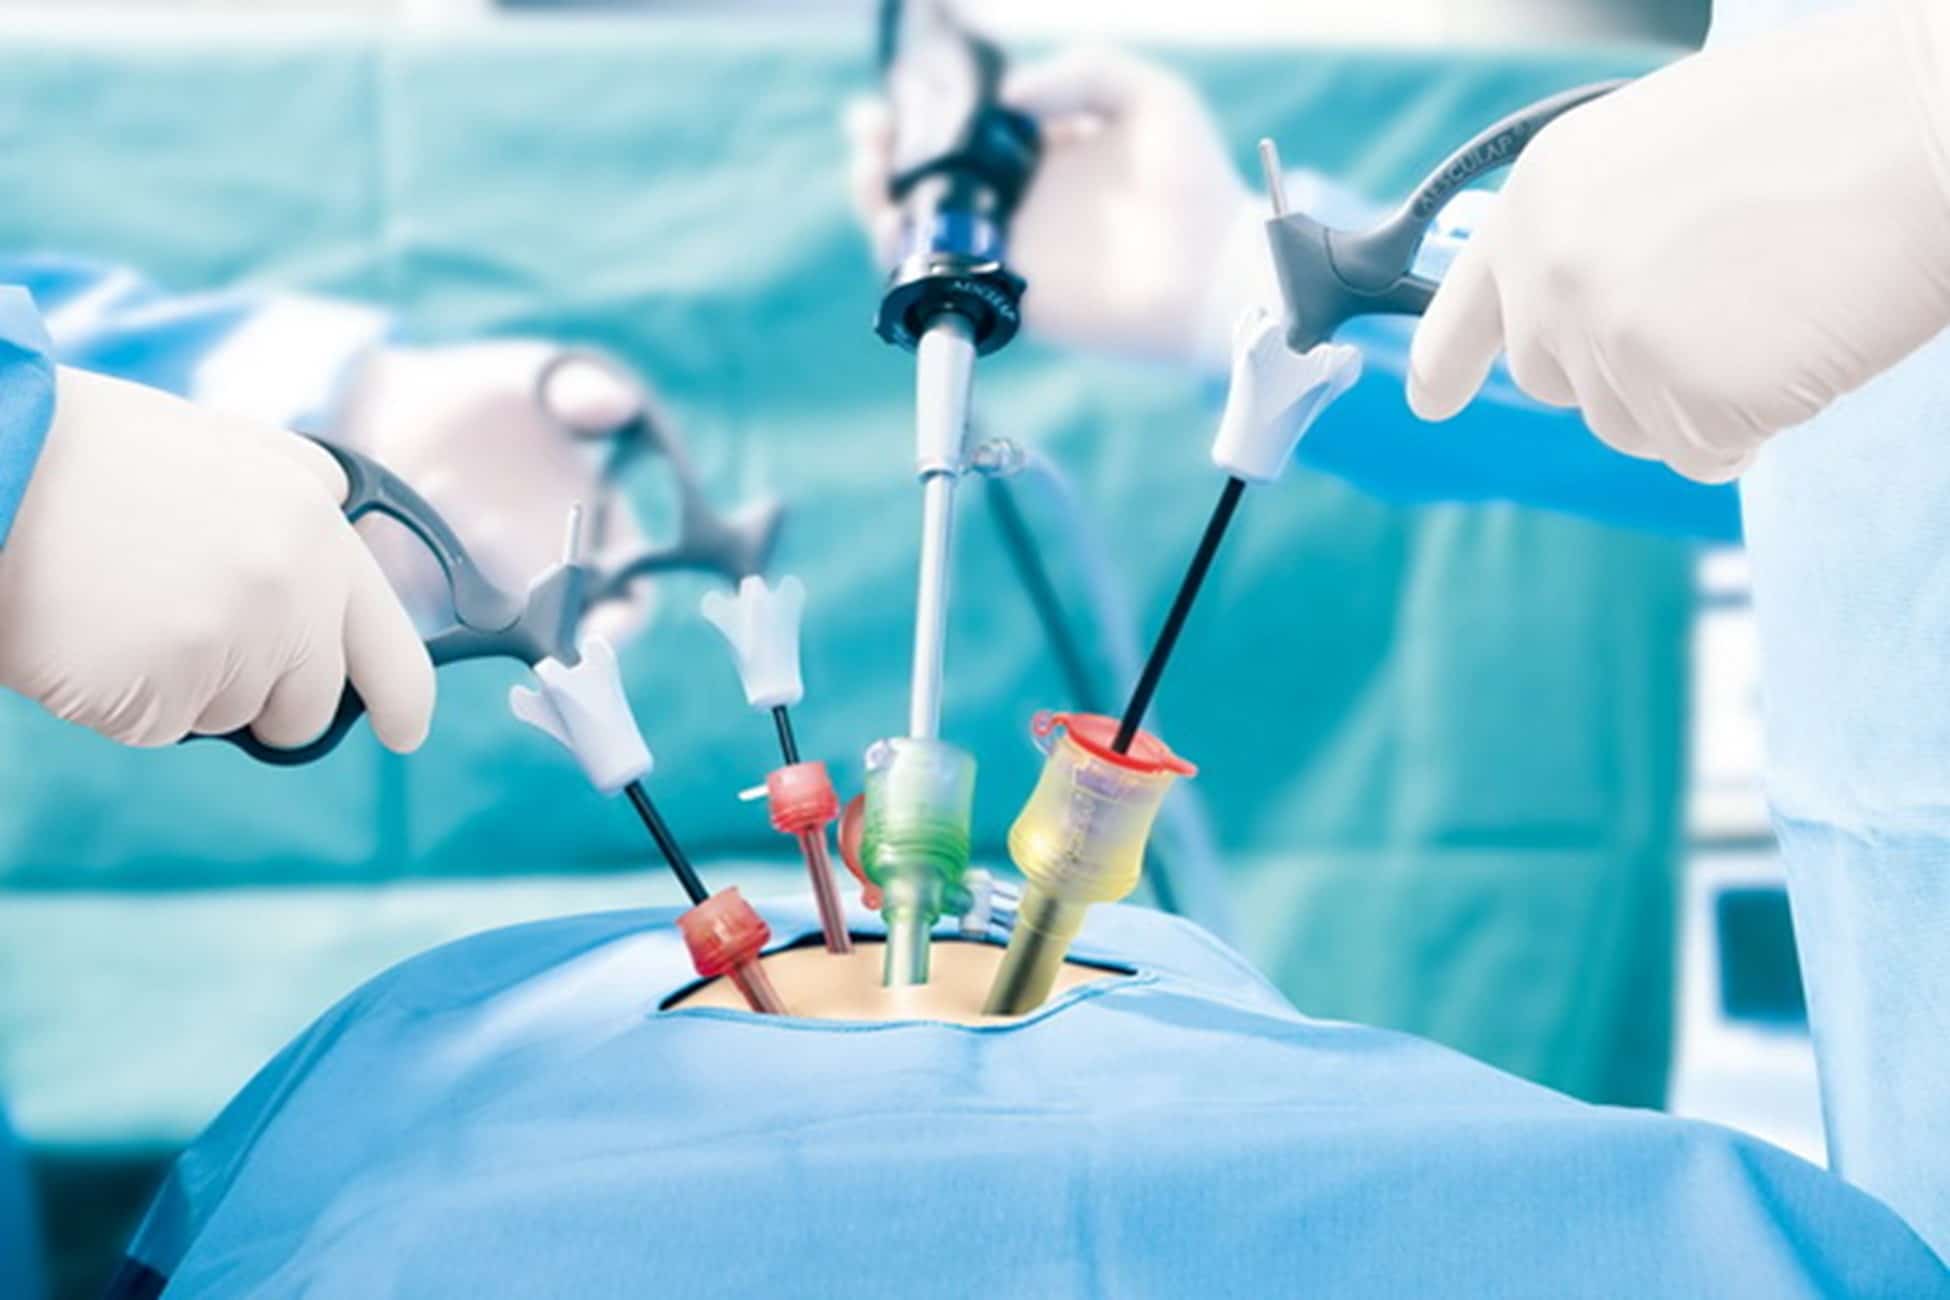

Read MoreGeneral surgery & Laparoscopy

General Surgery & Laparoscopy focuses on the diagnosis and surgical treatment of …